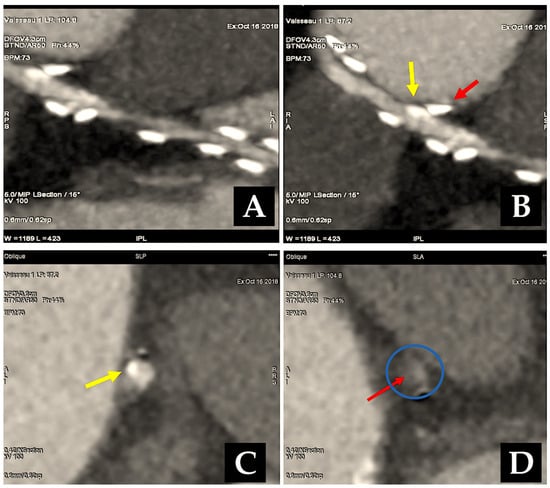

The results of a most recent investigation into our experience of radial artery grafting, comprising 819 patients, revealed that the five-year, ten-year, and fifteen-year survival rates were 95%, 81%, and 70%, respectively (Figure 5) [9,10,11,12,13].

Figure 5.

This shows how the radial artery can be used for CABG, either in a Y-shape for sequential grafting or for isolated grafting (A–F). (A): The RA is still open after five years. RA is used as a Y-graft technique for sequential anastomoses. (B,C): Y-graft technique on LAD and LCC2 at 6 years. (D,E): The blood flow is competitive, which causes the distal segment of the RA to shrink. The RA graft was anastomosed to the first and second obtuse branch of LCC at 8 years. (D): The circumflex coronary artery is free from significant narrowing, allowing unrestricted flow to the second obtuse branch. The first obtuse marginal is hardly visible. (E): The RA supplies the first obtuse branch (LCC1) with a string-like involution of its distal segment and no opacification of the second obtuse branch. (F): RA grafted on LAD and controlled at 18 years. Yellow arrow: 1. LITA; 2. Y-graft; 3. RA (LCC2). Abbreviations: CABG, coronary artery bypass grafting; LAD, left anterior descending; LCC, left coronary circumflex; LCC1, first obtuse branch; LCC2, second obtuse branch; RA, radial artery; RCA, right coronary artery.

Given the older age at operation, these results are more favourable than those of historical series of CABG, which included primarily vein grafts and demonstrated survival rates of 56% and 62%, respectively, at 15 years [115,116]. It is noteworthy that other studies have documented comparable long-term survival rates following RA grafting, with reported rates of 83% and 79% at 7 and 10 years, respectively [117,118,119]. A contemporary series of coronary bypass grafting with the LITA and SVG demonstrated a similar survival to that previously reported [120]. It is noteworthy that other studies have documented comparable long-term survival rates following RA grafting, with reported rates of 83% and 79% at 7 and 10 years, respectively [117,118,119]. A contemporary series of coronary bypass grafting with the LITA and SVG demonstrated a similar survival to that previously reported [120]. A freedom from the cardiovascular-related death rate of 89% at 15 years is observed following RA bypass grafting. Among the principal contributors to cardiac mortality within this cohort have been identified congestive heart failure, arrhythmia, stroke, and calcified aortic valve stenosis [13]. Our findings indicate that a preoperative ejection fraction below 40% represents a statistically significant predictive factor for late death [12].